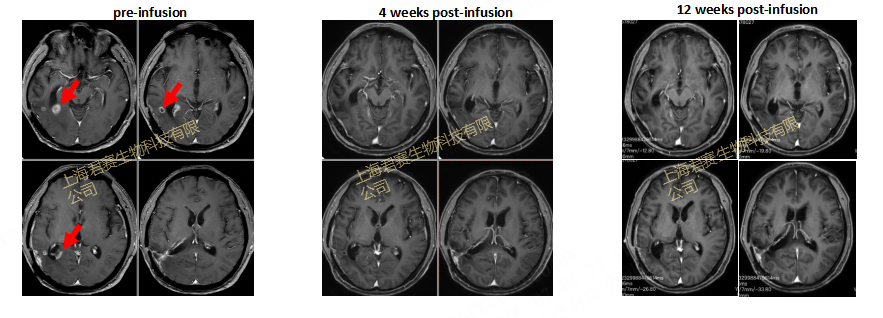

患者磁共振影像(MRI)变化

2023 年末,W先生和家属陷入绝望之际,命运的转机悄然降临。W 先生顺利加入 GC101 临床试验,接受 TIL 细胞回输治疗(细胞来源于其一年前手术取材培养)。回输后仅4 周,影像学显示其脑部肿瘤被完全清除,疗效评估为完全缓解(CR),后续再无复发,至今维持无瘤生存状态已超20个月。如今W先生早已摆脱了病床的束缚,重获新生,回归来之不易的正常生活。